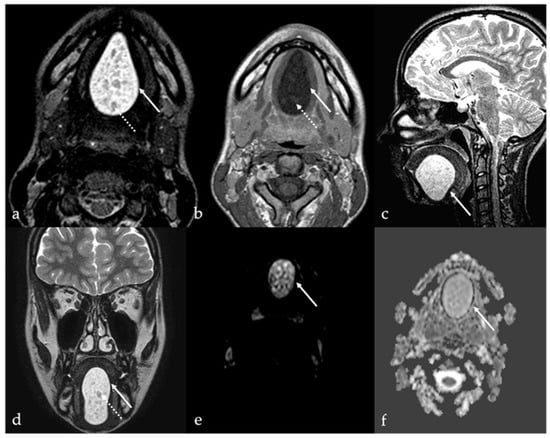

5.2. Lymphatic Malformations

| Lymphatic malformation [10,11] | Unilocular or multilocular, microcystic (<1 cm) or macrocystic (>1 cm) CT, MRI: no solid nodule with +CE MRI: high T2 SI, fluid-fluid levels | Other vascular malformations, dermoid cysts |